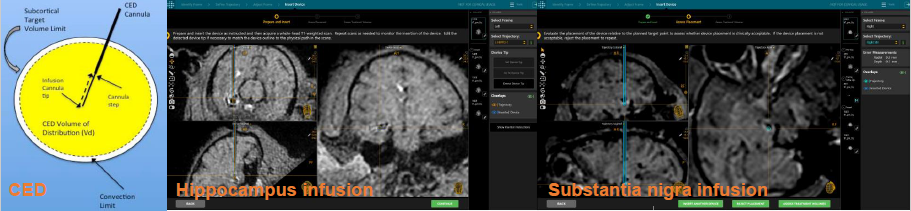

- Precision Platform for Trans-BBB Delivery: Utilizing intraprocedural MRI guidance, this platform enables precise and targeted convection enhanced delivery (CED) to specific brain structures. This technology is crucial for the growth of the neuro-therapeutic pipeline, ensuring accurate delivery of therapeutics across the blood-brain barrier.